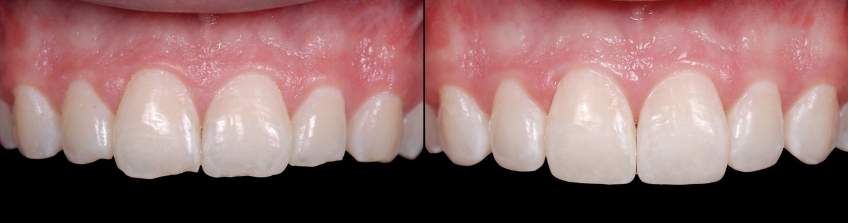

Your discussion should highlight the fact that as wear progresses, it will spread to more and more teeth in the mouth, making the potential treatment far more complex and expensive. It is also important to acknowledge that as tooth wear progresses, the teeth will often move — erupt, if you will — from dentoalveolar extrusion to maintain occlusal contact. This means the teeth are getting shorter and shorter and future treatment may involve possible crown lengthening to reposition gingiva and bone to expose more tooth (Figs. 1–5). If crown lengthening is necessary for a patient, Spear members can use the patient education video Crown Lengthening (Tooth Wear), which illustrates this well.

Examples of treatment options may be crown lengthening vs. intrusion to reposition overerupted anterior teeth (Figs. 6–10). You can explain each — or show the Spear Patient Education videos of each — then discuss with the patient why you believe one may be better for them.

As mentioned earlier, worn teeth typically don’t have indirect restorations, but amalgams or composites instead. This makes them easy to bond to, so you can create and try out your treatment plan with minimal to no tooth preparation and at a reasonable cost for the patient (Figs. 11–14).